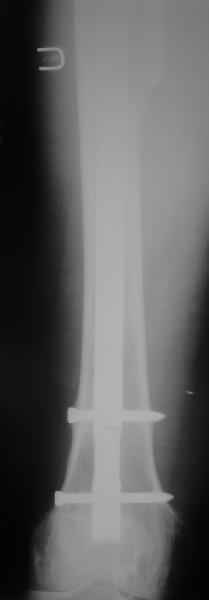

Это сплошной титановый стержень. На дистальном конце отверстия под кондуктор. На другом - канал под ножку глубиной 60 мм, стенки толщиной 2,5-3 мм. И там же продольный пропил, чтобы канал мог адаптироваться к ножке.

Обещанные ранее снимки Заранее спасибо.